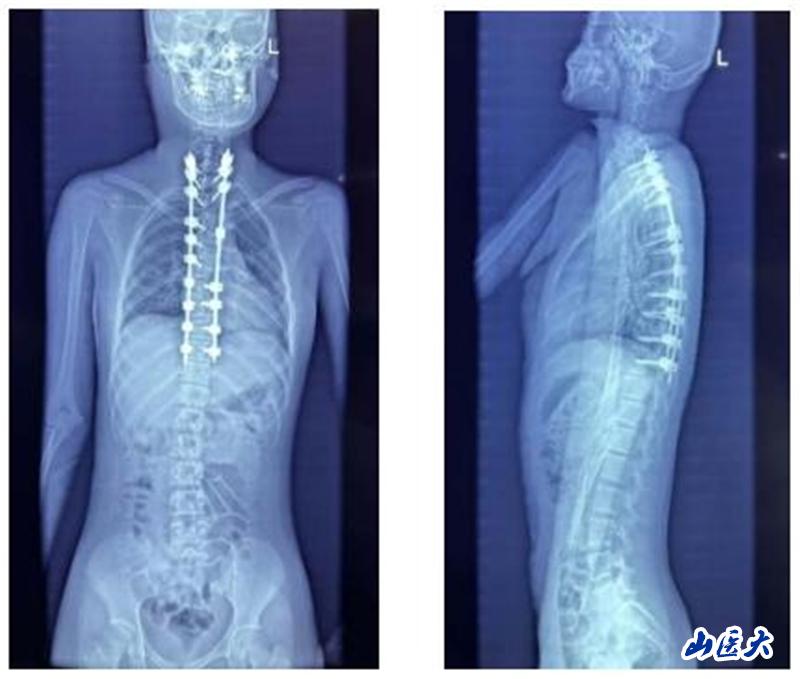

面对如此复杂病情,薛旭红教授与赵胜教授带领团队精心策划,为患者量身定制了个性化的手术方案。2024年12月27日,在主治医师董政权、麻醉医师、器械护士王淑珍和巡回护士杜娟的通力协作下,骨科团队成功完成了这场高难度、高风险的手术。

术后,患者恢复情况良好,身体逐渐康复。考虑到患者家庭经济困难,薛旭红教授主动帮助患者联系并申请北京海鹰脊柱健康公益基金会的救助。经过基金会评估,患者成功获得全额费用资助,实现了免费治疗。在医护团队和基金会的共同帮助下,小姑娘不仅免除了瘫痪的风险,更重新挺直了腰杆。